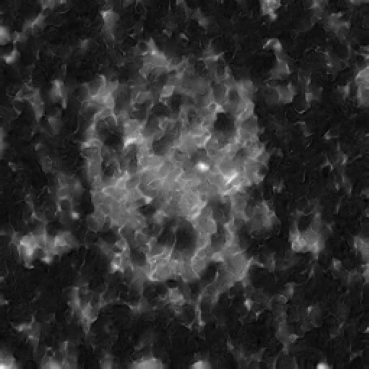

In our approach, we employ a compression factor of 4 to encode 3D medical images into the latent space. This level of compression reduces the spatial resolution of the original image (e.g., from 256×256 to 64×64 per slice), while still preserving the essential anatomical structures and semantic content. The latent representation at this scale offers a favorable trade-off between dimensionality reduction and semantic fidelity. Specifically, although fine-grained textures are simplified, key structural patterns (e.g., organ boundaries, lesion shapes) remain visually distinguishable and semantically coherent. As the compression rate increases, the latent representations become progressively more abstract. With lower compression (e.g., 2× or 4×), the latent features preserve key anatomical structures and spatial layouts, making them beneficial for our semantic image synthesis task in latent space, as the model can operate on compressed representations that retain sufficient semantic information without being overwhelmed by high-frequency noise. In contrast, higher compression rates (e.g., 8× or above) lead to a loss of fine-grained details and reduced semantic fidelity. The choice of a 4× compression thus ensures that the latent features are compact and meaningful, facilitating effective conditional generation while significantly reducing computational overhead. We therefore adopt a 4× compression as a compromise between computational efficiency and semantic preservation. The corresponding 2D slices in image space and latent space are shown in Figure 7.